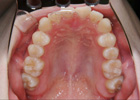

歯を抜かずに治療ができた例

治療前